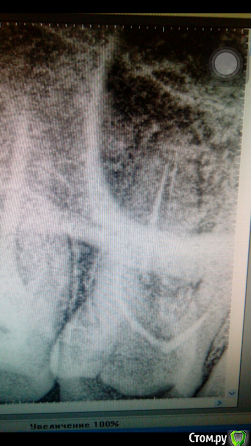

bozz903 Опубликовано 19 марта, 2016 Автор Поделиться Опубликовано 19 марта, 2016 Здравствуйте. С наступлением весны все тот же 16 зуб стал реагировать на температуру очень сильно. Также ноет сам по себе периодически. Боль не похожа на гиперчувствительность эмали.Сделал новые снимки. Что нибудь можно сказать по сравнение с теми, которые прикреплены в первом моем сообщении? Ссылка на комментарий

DmitrySH Опубликовано 19 марта, 2016 Поделиться Опубликовано 19 марта, 2016 (изменено) Низкая информативность снимков. Даже на ОПТГ качество лучше Изменено 19 марта, 2016 пользователем DmitrySH Ссылка на комментарий